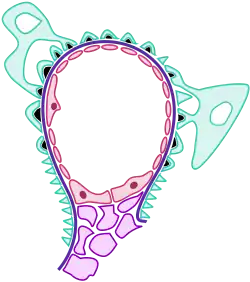

The pathophysiology of this disorder is consistent with an immune-complex-mediated mechanism, a type III hypersensitivity reaction. This disorder produces proteins that have different antigenic determinants, which in turn have an affinity for sites in the glomerulus. As soon as binding occurs to the glomerulus, via interaction with properdin, the complement is activated. Complement fixation causes the generation of additional inflammatory mediators.[2]

Complement activation is very important in acute proliferative glomerulonephritis. Apparently immunoglobulin (Ig)-binding proteins bind C4BP. Complement regulatory proteins (FH and FHL-1), may be removed by SpeB, and therefore restrain FH and FHL-1 recruitment in the process of infection.[13]